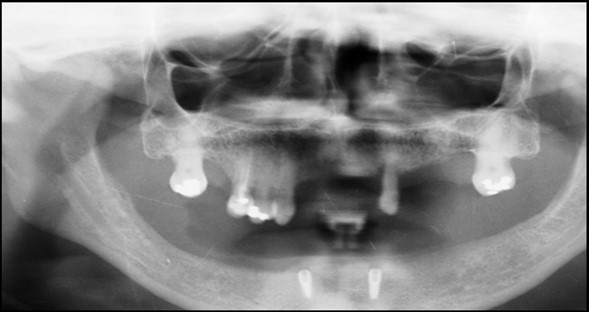

A 63 year old male patient came to our Aesthetics Dental Clinic ,Athens, Greece with the chief complaint of loose fitting lower denture with difficulty in mastication and speech. On examination, patient had resorbed alveolar ridge which lead to inadequate retention of the lower denture prosthesis and patient is known to be a previous denture wearer for past 1 year. The Orthopantomograph findings showed the presence of sufficient bone height and width (Figure 1), with dense cortical bone surrounded by dense trabecular bone. Thus implant supported overdenture was planned with two implants along with independent ball type attachments.

Figure 1.First Visit Pre-operative radiograph

Figure 6.Panoramic radiograph after the insertion of two implants